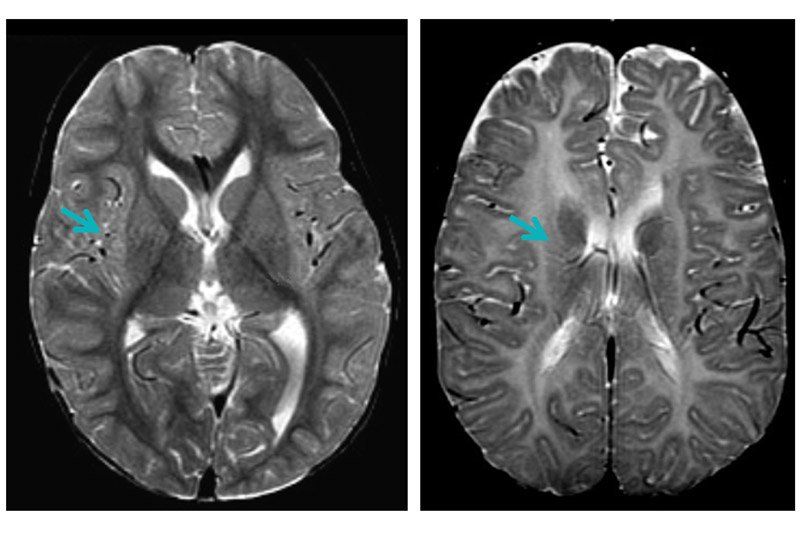

Pelizaeus-Merzbacher disease (PMD) is a rare genetic condition affecting boys. It can be fatal before 10 years of age and symptoms of the disease include weakness and breathing difficulties. PMD is caused by a disruption in the formation of myelin, a type of insulation around nerve fibers that allows electrical signals in the brain to travel quickly. Without proper signaling, the brain has difficulty communicating with the rest of the body. Despite knowing what causes PMD, it has been difficult to understand why there is a disruption of myelin formation in the first place.

However, in a CIRM-funded study, Dr. David Rowitch, alongside a team of researchers at UCSF, Stanford, and the University of Cambridge, has been developing potential stem cell therapies to reverse or prevent myelin loss in PMD patients.

Two new studies, of which Dr. Rowitch is the primary author, published in Cell Stem Cell, and Stem Cell Reports, respectively report promising progress in using stem cells derived from patients to identify novel PMD drugs and in efforts to treat the disease by directly transplanting neural stem cells into patients’ brains.